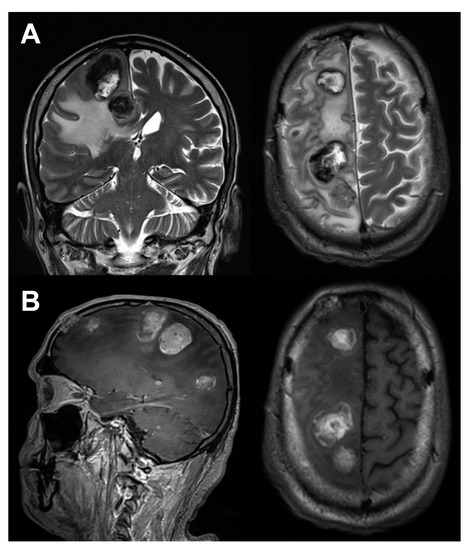

Brain Metastases Unresponsive to Immunotherapy Detected by 18F-FDG-PET/CT in a Patient with Melanoma

Fonti, R.; Pellegrino, S.; Mainolfi, C.G.; Matano, E.; Del Vecchio, S. Brain Metastases Unresponsive to Immunotherapy Detected by 18F-FDG-PET/CT in a Patient with Melanoma. Diagnostics 2020, 10, 410. https://doi.org/10.3390/diagnostics10060410